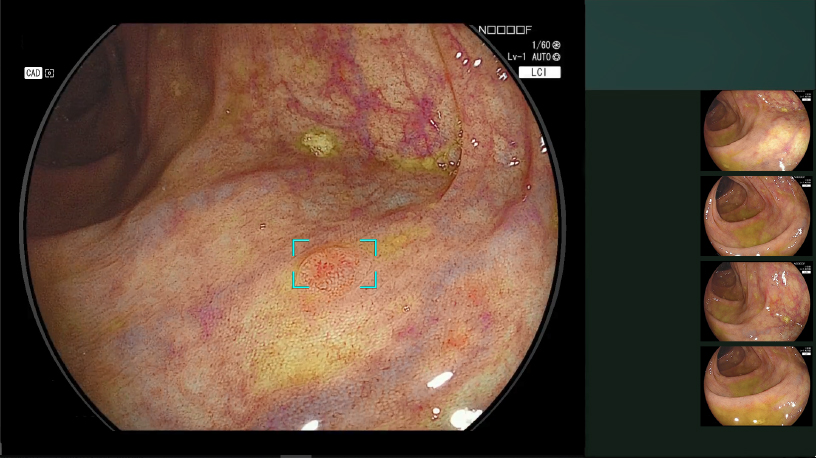

照射した光と画像処理を組み合わせる「マルチライトテクノロジー」により、粘膜表層の微細な血管や構造を強調するなど、目的に応じた観察画像を作り出す4色のLED光源搭載の内視鏡システム『ELXEO7000』を導入しています。

短波長狭帯域光と白色光の成分をバランスよく照射。そのあとソフトウェアにより、赤みを帯びた色はより赤く、白っぽい色はより白くなるように色の拡張・縮小を行い、粘膜の微妙な色の違いを強調します。これにより腫瘍や炎症の検出が容易となり、通常観察と比べ1.67倍上部の腫瘍性病変の拾い上げが可能と報告されました(多施設無作為比較試験LCI-FIND試験より)。